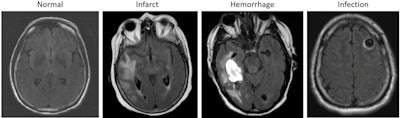

The researchers collaborated with Diagnosticos da America SA (DASA) of Barueri, Brazil, to develop a deep-learning algorithm that uses T2-weighted fluid attenuated inversion-recovery (FLAIR) images to categorize brain MRI scans as either "likely normal" or "likely abnormal."